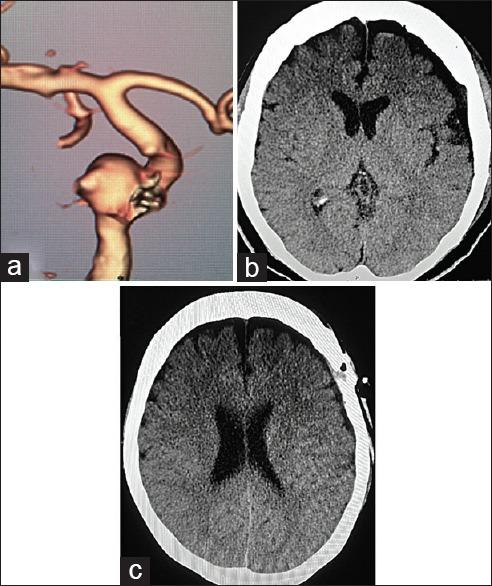

One of the underreported complications of clipping of unruptured aneurysm is chronic subdural hematoma/hygroma (CSDH). It can cause sudden deterioration and might need emergency evacuation. Recently, very few papers have studied its incidence and predisposing factors. We are reporting our institutional experience of it along with the study of its risk factors and possible pathogenesis.

Totally 91 postoperative patients of unruptured aneurysms were retrospectively analyzed. Totally 21 patients had CSDH who were operated. In rest seventy patients, there was no CSDH.

Male sex, old age, anticoagulant use, presence of pneumocephalus and dead space were significantly associated with occurrence of CSDH, whereas arachnoidoplasty significantly protected against it. There was no significant relation of CSDH with Gorei-san use.

未破裂动脉瘤夹闭术未被充分报道的并发症之一是慢性硬膜下血肿/积液(CSDH)。它可导致病情突然恶化,可能需要紧急引流。最近,很少有论文研究其发生率和易感因素。我们报告我们机构对此的经验以及对其危险因素和可能发病机制的研究。

对91例未破裂动脉瘤术后患者进行回顾性分析。共有21例接受手术的患者发生了CSDH。其余70例患者未发生CSDH。

男性、老年、使用抗凝剂、存在气颅和死腔与CSDH的发生显著相关,而蛛网膜成形术对其有显著预防作用。CSDH与使用葛根汤无显著关系。